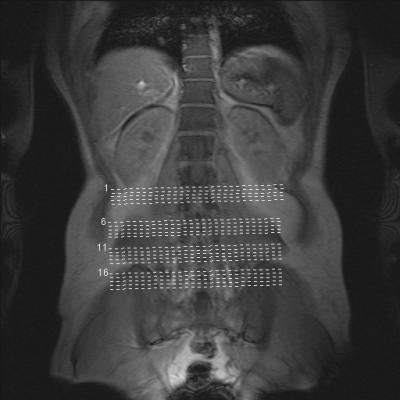

war wegen hodenschmerzen beim urologen, dieser schaute sich u.a. meinen rücken an, schickte mich dann zum orthopäden und dort wurde dann u.a. ein mrt gemacht. habe noch keinen weiteren termin zur besprechung bekommen, aber die bilder schon mal mitbekommen.

diese sind nun im anhang und mich würde interessieren ob ihr hier vielleicht schon was dazu sagen könnt.

mich würde aufgrund der bilder nur hier mal interessieren ob das eine skoliose ist.

- forum_photo1.jpg (20.82 KiB) 2599 mal betrachtet

Eine Skoliose (seitliche Verbiegung der WS) ist für mich nicht zu erkennen. Wenn das zweite Bild eine seitliche Aufnahme der LWS ist, sieht man dort eine deutliche Lordose.

Ich erkenne auch keine Skoliose, ABER MRT´s werden ja im Liegen aufgenommen und da wird der Rücken ganz anders belastet, so dass liegende Aufnahmen zur Diagnostik von Skoliose oder auch Kyphose/Lordose nicht geeignet sind. Für Bandscheibenschäden und Strukturen etc. ist ein MRT sinnvoll, aber nicht zur Bestimmung einer Skoliose. Dazu benötigt man Röntgenaufnahmen im Stehen von vorne und von der Seite (Ganzaufnahmen!!). Wie kommst du denn auf Skoliose, hatte man bei dir den Verdacht??